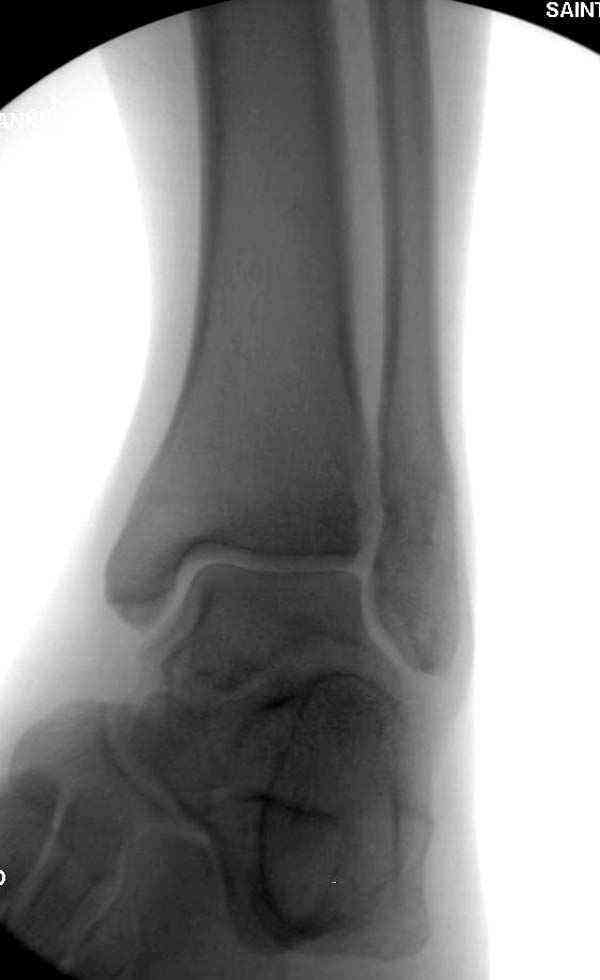

Коллеги правы, что при рутинных переломах достаточным бывает обычные снимки с мортизом. А стрессовые рентгенограммы могут уточнить, есть ли разрыв синдесмоза.

Здесь несколько частных случаев: перелом голеностопа со сравнительными снимками и разрыв синдесмоза, а также медиальная Hook пластина.